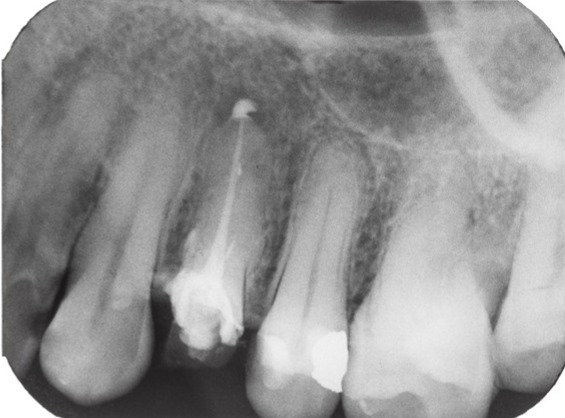

★치근단 절제술은 일반적인 신경치료로 해결되지 않는 치근단 부위의 감염 또는 염증을 외과적으로 제거하는 술식입니다. 말 그대로 치아 뿌리 끝을 잘라내고 병변을 제거하는 외과적 시술입니다.

2. 치근단 병소 존재: 치근 끝에 낭종, 육아종, 고름집(농양) 등이 있을 때

3. 치근단 절제: 치아 뿌리 끝 약 2~3mm를 절단하고 병소 제거

4. 역충전: 치근 끝을 다시 밀폐하기 위해 충전물을 채워 넣기